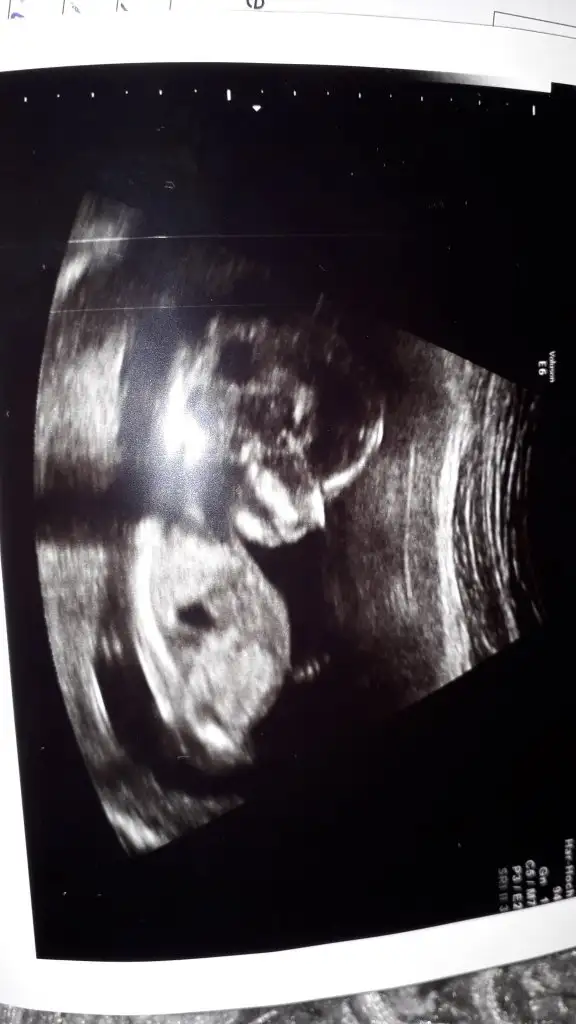

Kız gibi birde 11 yada 12 hafta usg paylaşırmısınızTeyzeleri bizde tahmin bekliyoruz 13+6 gunlukbizim grupta da tahmin edenler oldu bakalim siz ne diyeceksiniz

Net degil kız diyecem emin olamıyorum 12 hafta usg paylaşın bu kaç haftalıkYaa acayip merak ettim ultrason kagidinin resimlerini yukluyorum kizlar bizim tahminlerimizi de alalim